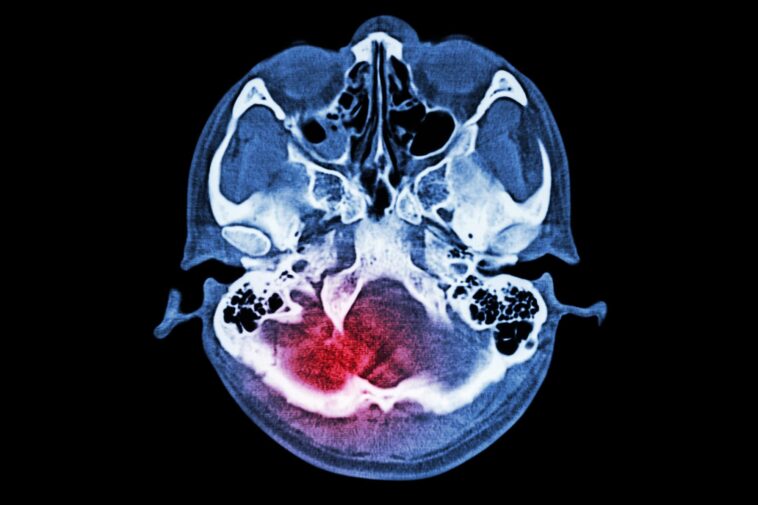

Un accident vasculaire cérébral ischémique survient lorsque le flux sanguin vers une partie du cerveau est interrompu, privant les cellules cérébrales d'oxygène et de nutriments. Sans traitement rapide, les cellules cérébrales peuvent mourir, entraînant des dommages permanents au cerveau et à ses fonctions. L'accident vasculaire cérébral est l'une des principales causes de décès et d'invalidité dans le monde, touchant des millions de personnes chaque année.